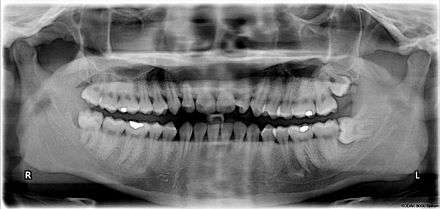

X-ray of the teeth and jaw showing the normal permanent teeth. The last two teeth on the patient's left (the dentist's right), 28 and 38 - the maxillary and mandibular third molars (popularly the upper and lower wisdom teeth) are severely impacted.